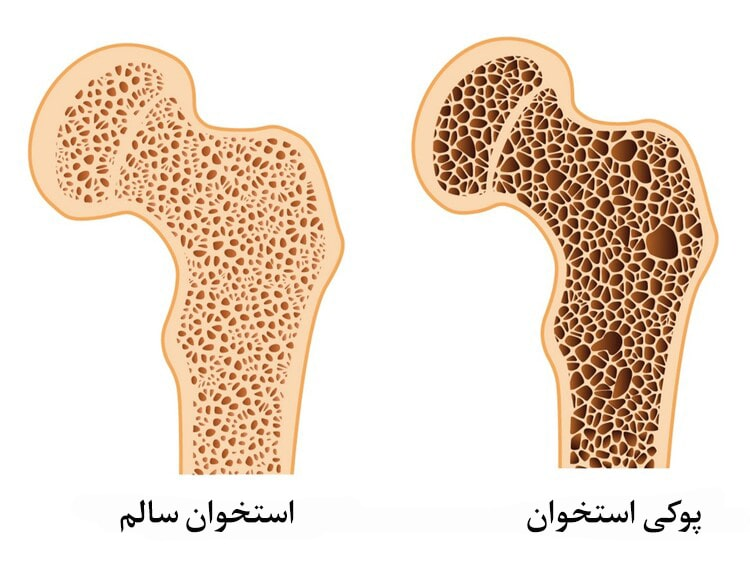

این بیماری به «بیماری خاموش» معروف است، زیرا تا زمانی که شکستگی رخ ندهد، معمولاً علائم خاصی نشان نمیدهد. استخوانها بافتی زنده هستند که بهطور مداوم در حال تجزیه و بازسازیاند؛ استخوانهای قدیمی شکسته و استخوانهای جدید جایگزین آنها میشوند.

رشد توده استخوانی معمولاً تا حدود سن ۳۰ سالگی ادامه دارد و پس از آن متوقف میشود، بنابراین حفظ و محافظت از این توده تا حد امکان اهمیت زیادی دارد. با افزایش سن، فرآیند جایگزینی استخوان سالم کندتر شده و ساختار استخوان که شبیه به لانه زنبور است، دچار تغییر میشود. در پوکی استخوان، فاصله بین ساختارهای لانهزنبوری استخوان افزایش یافته و پوسته خارجی آن نازک و شکننده میشود، که منجر به شکستگی آسانتر استخوانها میگردد.